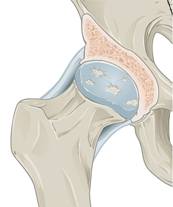

Fig. 9.10 Osteoarthritis. (Sources of images

and videos below. Used with permission.)

Note: (1) the progressive roughening of the round ball and its socket,

(2) the decreasing clear space (cartilage and fluid) between them,

(3) and the extra rough bone (white material) around the joint.

Description English:

Osteoarthritis in the hip. This is an edited version of the source

image made for use in the "Anatomist" iOS and Android app and shared

here under the terms of the source image's Share Alike Creative Commons

license.